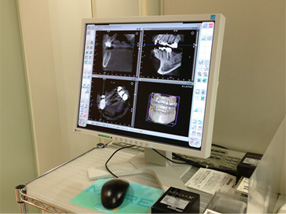

CTスキャンしたお客様の歯の状態のデータを専用のCAD(3D)ソフトで作成し、

コンピュータ上でインプラント治療のシミュレーションを行います。

それにより、事前にインプラントを入れる位置を決めることができ、

より安心安全に外科処置を行う事も可能になります。

歯科用のCTスキャン装置は、従来の機器よりも放射線量が少なく安全に診断を行えます。

自分の歯や骨の状態を、3D画像で立体的に見ることができるので、詳細な診査、診断が可能になります。

正確な診断と安全確実な治療のために歯を支えている周りの骨の状態を知ることは大切なことです。

これからのインプラント治療にCT検査はかかせません。

CT画像は、アゴの骨の立体的な形態や、神経の位置把握、骨密度の診査などに利用されます。

インプラントの治療を行う前だけでなく、治療を終えたあとにも撮影を行って状態を確認します。